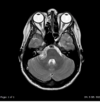

What imaging is used in this picture? [1]

A

dopamine transporter (DaT) - DaT scan